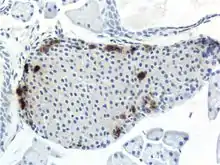

Through different microscopy techniques, the structural related details of PP cells have been able to be better understood. This is inclusive of how big they are, what their cellular membranes look like, the proteins associated with them, and even their size. PP cells are elongated cells. Another one of these details can be noted in insulins secretory granules, or container like buds, that store insulin within a cell. In PP cells, the size of the insulin granules are smaller and spherical and similar to those in alpha cells. This is noted in human PP cells, but different animals have been shown to have different sized granules compared to humans, like rodents. In cats and dogs, PP cells have large granules.[8] In rats, PP cells have few granules, similar to humans. In dogs, some PP cells are located in the walls of the antrum of the stomach.[3]